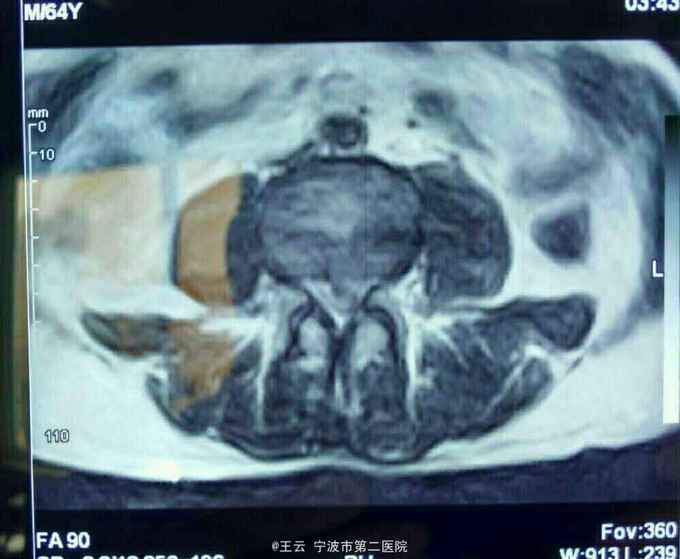

腰3/4椎间盘脱出向下高度游离

患者,女,41岁,因“左下肢放射痛麻木三个月”入院。三个月前有过度劳累史。

诊断:L3/4椎间盘脱出 治疗:经椎间孔入路椎间孔镜下髓核摘除,射频消融